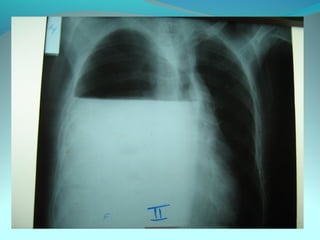

Opacité latéro_trachiale et hilaire droite grossierement arrondie de

6cm de diam dense et homogene

 la limite interne se confend avec le mediastin et la limite externe

nette convexe vers le mediastin

elle confond avec le mediastin évoquant une image mediastinale

Par ailleur on note:

Une surrélevation de la coupole diaph

Un coblement …..

DIAGNOSTIC:

Lymphome H ou NH

Volumineuse ADP tuberculeuse ou sarcoidosique